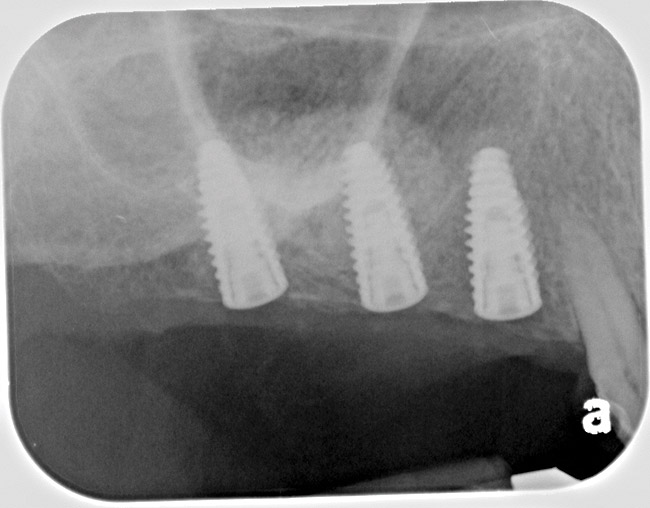

Fig 14. Peri-apical X-ray of the site immediately following sinus floor elevation and implant insertion.

Figure 14